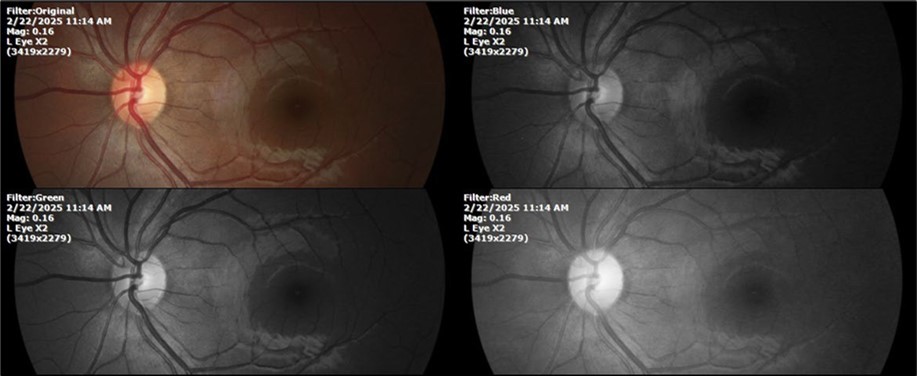

There is no pain, only minimal discomfort, and my vision has improved (Figure 20, Figure 21, Figure 22, Figure 23, Figure 24)

Figure 23.The mirror reflection of the left eye, without anomalies.

Figure 24.The eye that was not affected by the trauma (left side) remains in good condition.